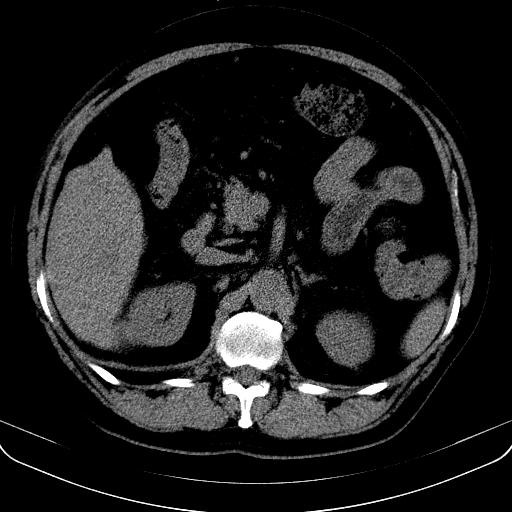

以下是引用jia119在2008-3-5 13:31:00的发言:[br]肝内多发片状低密度影,密度不均,我还是考虑肝ca可能,另肝内小囊肿,胆囊增大。

以下是引用形影不离在2008-3-5 12:18:00的发言:[br]肝硬化伴门脉高压征,肝内占位待排,增强再说.

以下是引用随光逐影在2008-3-5 21:11:00的发言:[br]肝硬化伴门脉高压(食管下段静脉曲张),肝癌不排除。建议:行ct增强扫描检查。

以下是引用同在2008-3-5 13:56:00的发言:[br]考虑肝癌可能性大,胆囊增大.